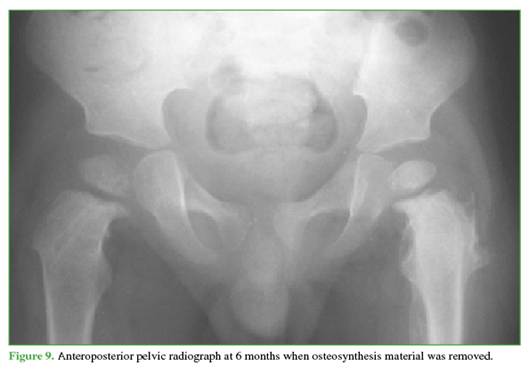

Figures 9 and 10 show the imaging follow-up at 6 and 24 months after removal of the osteosynthesis material.